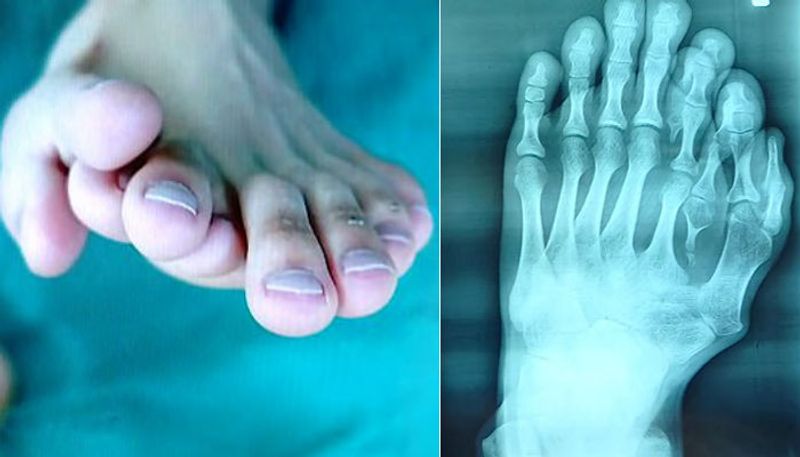

കാലില് ഒമ്പത് വിരലുകളുമായി ഒരു യുവാവ്. കേള്ക്കുമ്പോള് ഒരുപക്ഷേ ആദ്യം നിങ്ങളില് കൗതുകമായിരിക്കാം തോന്നിയിരിക്കുക.. എന്നാല് ഈ അപൂര്വ്വാവസ്ഥ കൊണ്ട് നിരവധി ബുദ്ധിമുട്ടുകളാണ് ചൈനക്കാരനായ അജുന് എന്ന യുവാവ് തന്റെ ഇരുപത്തിയൊന്ന് വര്ഷക്കാലത്തെ ജീവിതത്തിനിടയില് അനുഭവിച്ചത്.

എന്നാല് ഇരുപത് വയസ് കടന്നതോടെ അജുന് തന്റെ തീരുമാനം വീട്ടുകാര്ക്ക് മുന്നില് അവതരിപ്പിച്ചു. ഒടുവില് അവര്ക്ക് അവന് മുമ്പില് വഴങ്ങുകയല്ലാതെ മറ്റ് മാര്ഗമുണ്ടായിരുന്നില്ല. അപ്പോഴും വെല്ലുവിളികളേറെയായിരുന്നു. ഇടതുകാലില് നാല് വിരലുകളാണ് അധികമായിട്ടുള്ളത്.

ഇതില് തള്ളവിരല് പുറത്തേക്ക് തള്ളിനില്ക്കുന്ന വിരലുകളുടെ കൂട്ടത്തിലായിരുന്നു. ആദ്യം കണ്ട ഡോക്ടര്മാരെല്ലാം പറഞ്ഞത്, പുറത്തേക്ക് തള്ളിനില്ക്കുന്ന നാല് വിരലുകള് നീക്കം ചെയ്യാമെന്നാണ്. എന്നാല്, തന്റെ കാല് കാണുമ്പോള് മനോഹരമായിരിക്കണമെന്ന് അജുന് നിര്ബന്ധമുണ്ടായിരുന്നു.

അങ്ങനെ ആഗ്രഹത്തിനൊത്ത് വിജയകരമായി ശസ്ത്രക്രിയ നടത്തിത്തരാന് കഴിവുള്ള ഡോക്ടര്മാരെ തേടി, ഫോഷന് എന്ന സ്ഥലത്തെ ഒരാശുപത്രിയില്, അജുനും കുടുംബവും എത്തി. അവിടെ ഡോ. വു ക്സിയാംഗിന്റെ നേതൃത്വത്തില് ശസ്ത്രക്രിയ നടത്താമെന്നും ഒട്ടും വികലമാക്കാതെ തന്നെ കാലിനെ സാധാരണരൂപത്തിലാക്കാമെന്നും ഏറ്റു. നീണ്ട ഒമ്പത് മണിക്കൂറത്തെ ശസ്ത്രക്രിയയായിരുന്നു. അതിമനോഹരമായ തരത്തിലാണ് അധികമായ വിരലുകളെ ഡോക്ടര്മാര് നീക്കം ചെയ്തിരിക്കുന്നത്. ഇതിന്റെ ചിത്രങ്ങളും ഇപ്പോള് ആശുപത്രി അധികൃതര് പുറത്തുവിട്ടിട്ടുണ്ട്.

കൈകളിലും കാലുകളിലുമെല്ലാം അധികവിരലുകളുണ്ടാകുന്നതും, അവ ശസ്ത്രക്രിയയിലൂടെ നീക്കം ചെയ്യുന്നതുമെല്ലാം സാധാരണമാണെന്നും എന്നാല് ഒമ്പത് വിരലുകളുള്ള ഒരാളുടെ ശസ്ത്രക്രിയ ചൈനയില് തന്നെ മുമ്പ് നടന്നിട്ടുണ്ടോയെന്ന് വ്യക്തമല്ലെന്നും ഡോ. വൂ ക്സിയാംഗ് പറയുന്നു. അജുന് സുഖം പ്രാപിച്ചുവരികയാണെന്നും, വളരെ വൈകാതെ നടക്കാന് കഴിയുമെന്നാണ് പ്രതീക്ഷിക്കുന്നതെന്നും ഇവര് കൂട്ടിച്ചേര്ത്തു.